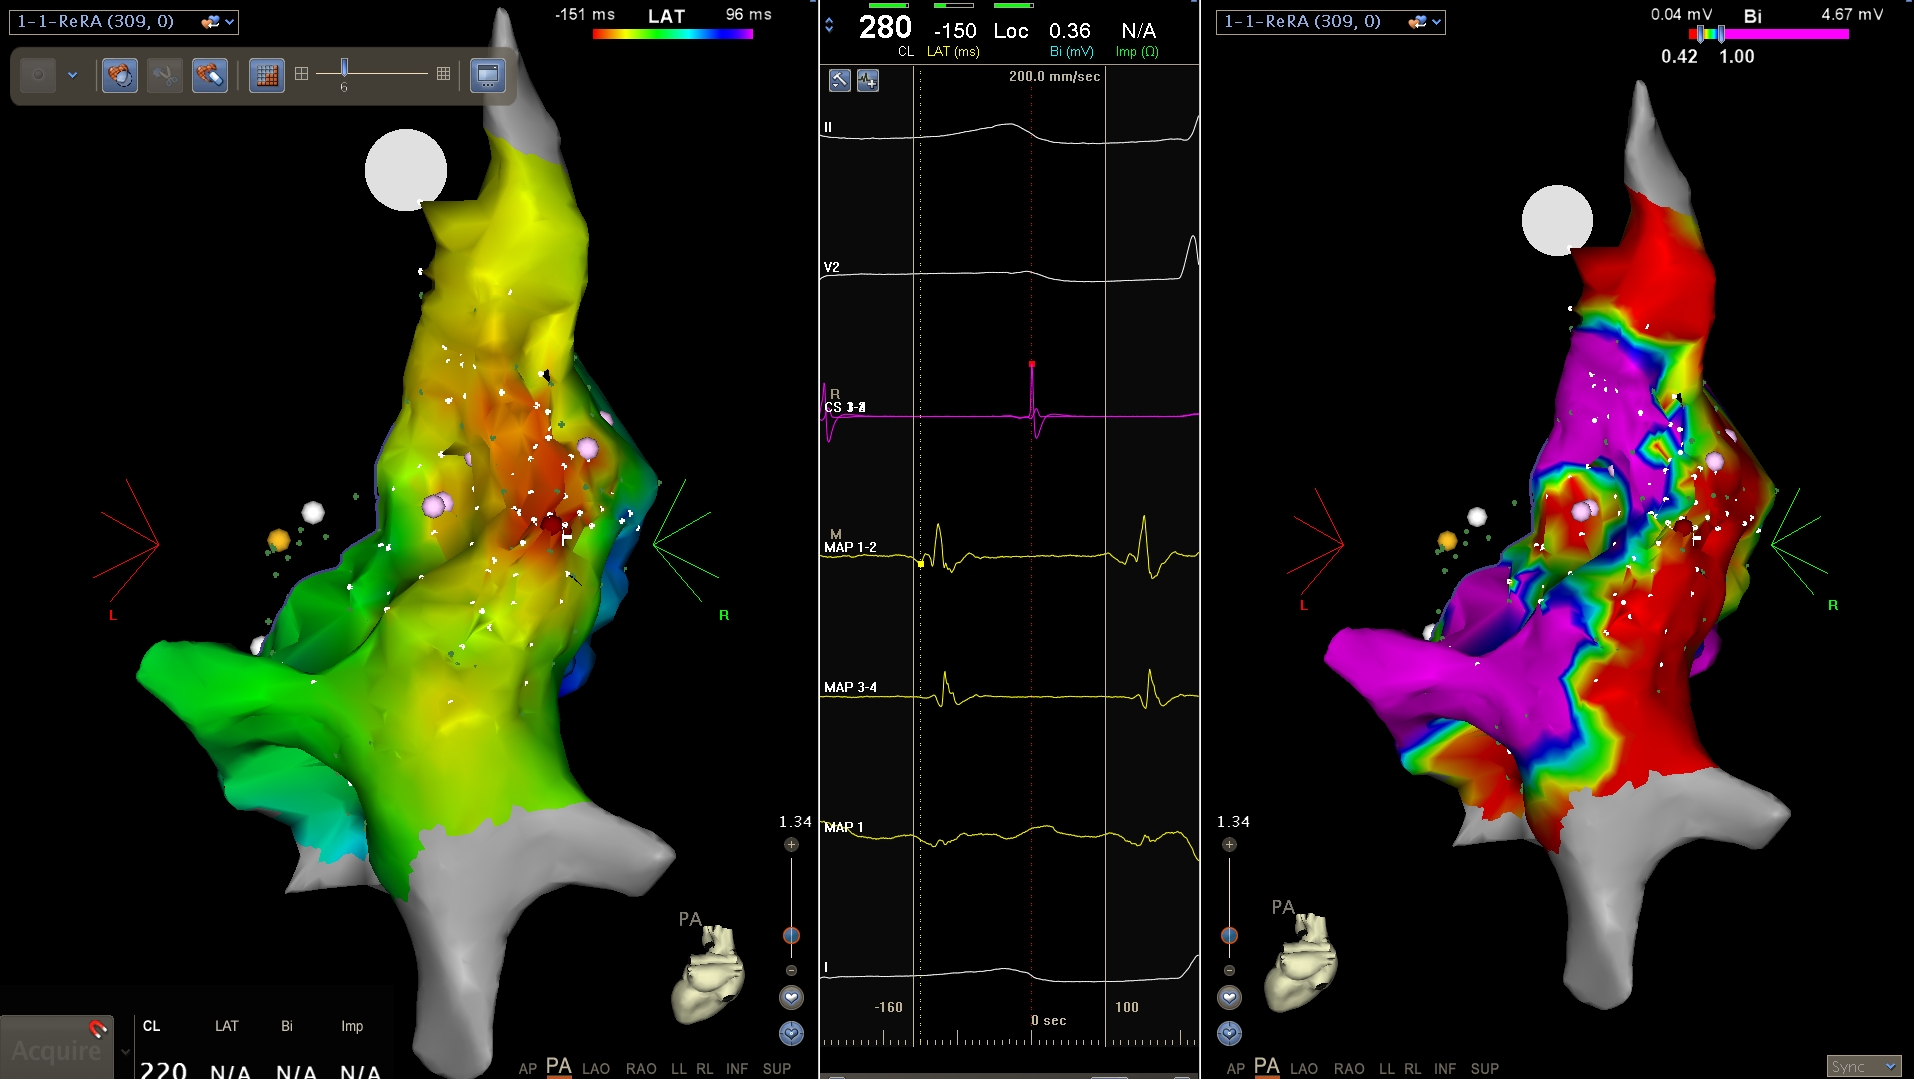

Activation map

• Isochronal map

• Activation time in relation to fixed reference

• Similar activation times marked with same colour

example - reentry

peritricuspid_vt.jpg

Kumar S, Subramanian A, Selvaraj RJ. Peritricuspid reentrant ventricular tachycardia in Ebstein's anomaly. Europace. 2014 Nov;16(11):1633